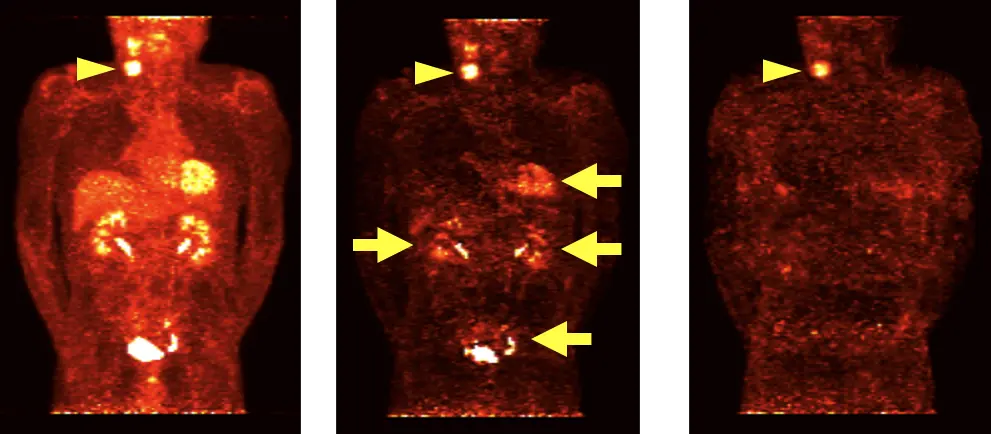

以下の図において、左の今回PET画像では頚部の真病変 (▶) のほかに、肝や心筋などの正常臓器にも多数の生理的集積が描出されています。中央の単純な差分画像においても、真病変のほかに偽陽性として心筋や尿路も描出されてしまっています (→)。右の提案手法では真病変のみが描出できているのが分かります。